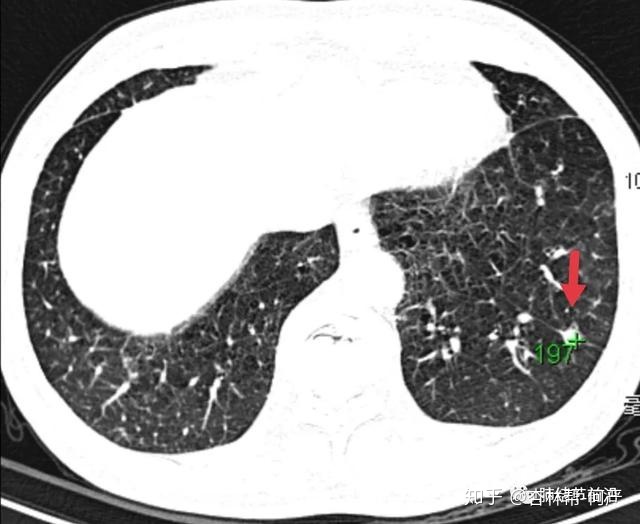

结节2:8mm实性结节,边界稍毛糙,支气管进入,CT图像提示为肺癌可能。

结节2:CT值为214,诊断为纤维灶结节。